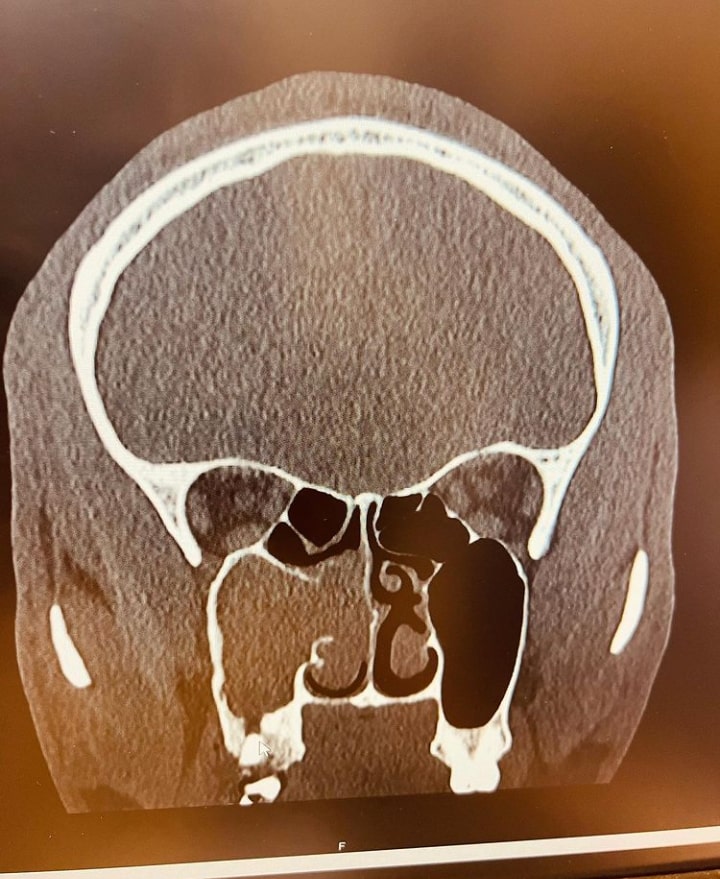

Half of my right face/nostril was blocked and I was only breathing from my left nostril. At this stage I wake up with mucus from my right nostril every single day. At this point, my only option was to have a surgery as recommended by my Doctor.

PS : The grey area of the scan photo is the blocked part of my Face/Nostril. Big thanks to my friends and loved ones that took care of me when I was sick. May Almighty God meet you at your point of needs.”